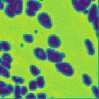

The field of computational pathology has witnessed great advancements since deep neural networks have been widely applied. These deep neural networks usually require large numbers of annotated data to train vast parameters. However, it takes significant effort to annotate a large histopathology dataset. We propose to build a data-efficient model, which only requires partial annotation, specifically on isolated nucleus, rather than on the whole slide image. It exploits shallow features as its backbone and is light-weight, therefore a small number of data is sufficient for training. What's more, it is a generative compositional model, which enjoys interpretability in its prediction. The proposed method could be an alternative solution for the data-hungry problem of deep learning methods.